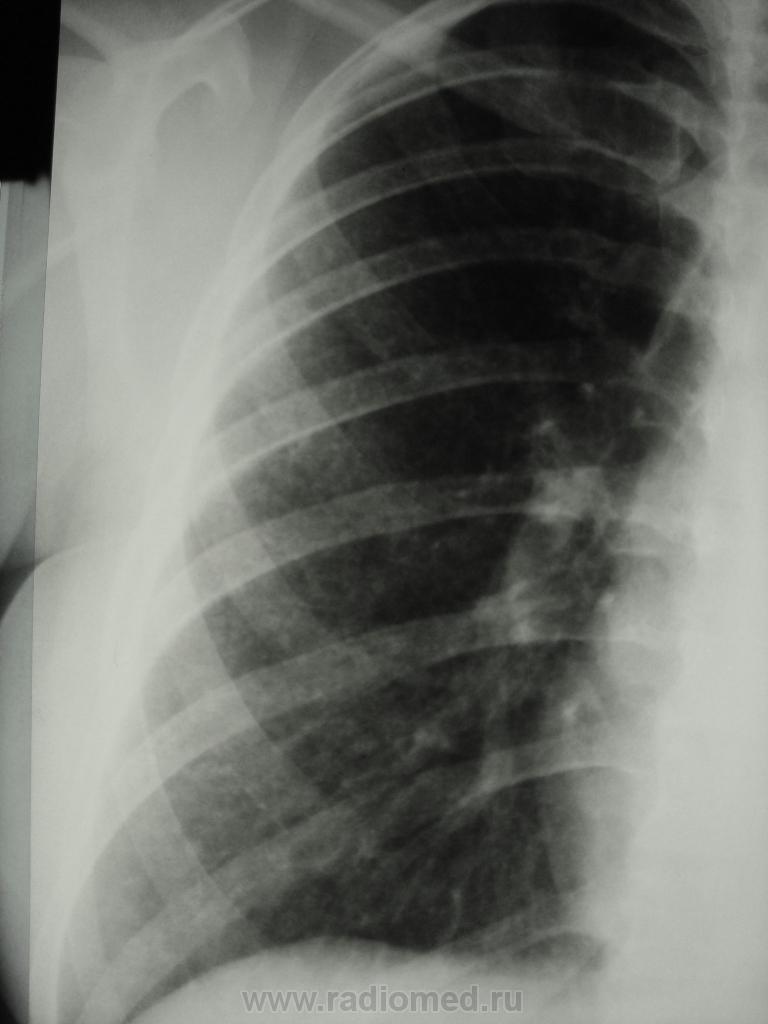

девушка 1985 г.р. дообследована после профилактической флюорографии, на КТ написали гистиоцитоз. Диагноз пока не подтвержден. Жалоб не предъявляет, курит в течение 8-9 лет. консультирована у фтизиатров, свою патологию они исключили.

На мой взгляд, выражены два компонента:

- преимущественно мономорфная диссеминации;

- интерстициальный компонент.

По рентгенограммам, создается впечатление превалирования "изменений", преимущественно, в средних и нижних отделах легочных полей.

Но, КТ, по всей видимости, свидетельствует, именно, о диффузности процесса, с некоторым превалированием в отдельных отделах.

Изменения диффузны. По rg более выраженны в нижних отделах, за счет марсива тканей. Ждем анализ мокроты и промывных вод.